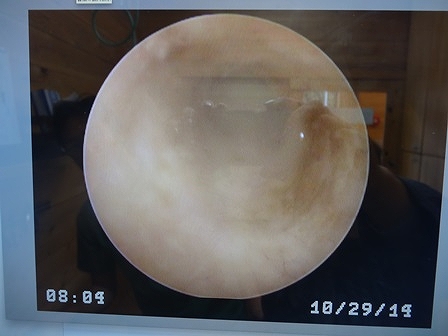

終わってから、画像を見せてもらって

この2枚は昨日のもの

撮影の仕方が悪くて、乳母とカメラが写っちゃったね

これは今日のもの

昨日より、綺麗になっているよって

洗浄液を耳に入れて、スポイトで吸い取ると

昨日は、濁っていた水が、今日はそれほど汚れていなかったらしい

このまま、洗浄続ければ、綺麗になるかなぁ~~

早く、鼓膜が見えるようになりますように![]()